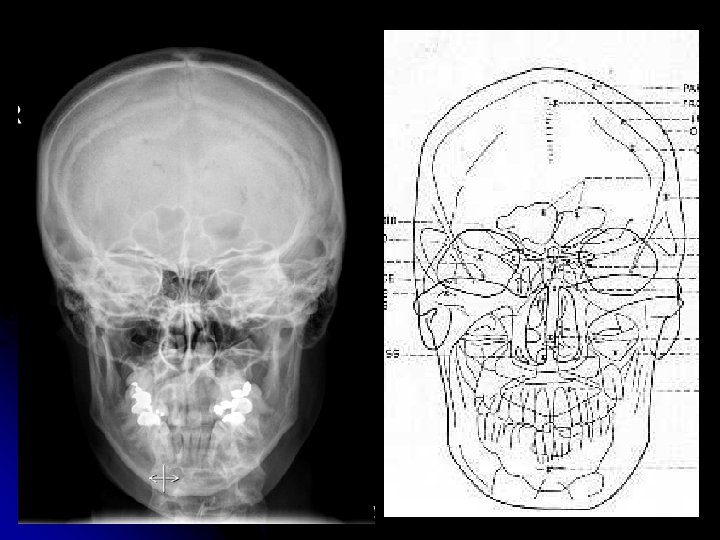

RTG anatomie lbi l PA (AP) projekce, bočná projekce (pravá, levá), semiaxiální projekce l projekce dle Towna

Lebka - projekce • sagitální projekce - AP - PA • bočná projekce (frontální) - pravá - levá • axiální - zhora - zdola

Lebka – projekce • šikmá – 30°, 45°, 60° - přední – pravá, levá - zadní – pravá, levá • tangenciální • oblast zájmu co nejblíže kazetě!!!

Lebka – zadopřední projekce